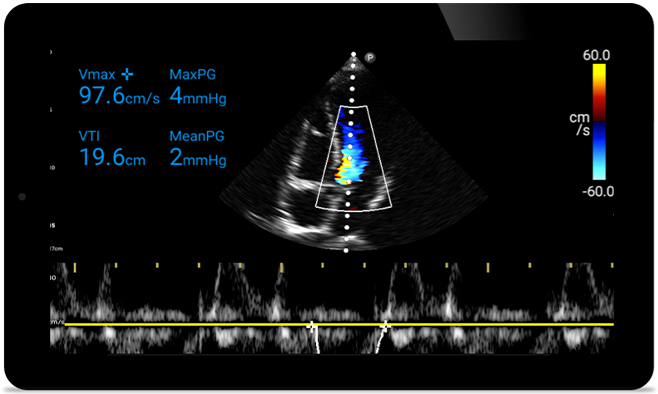

Act faster to protect their heart

When seconds count, portable ultrasound can make the difference. Lumify can provide the high-definition imagery you need whenever and wherever you need it.